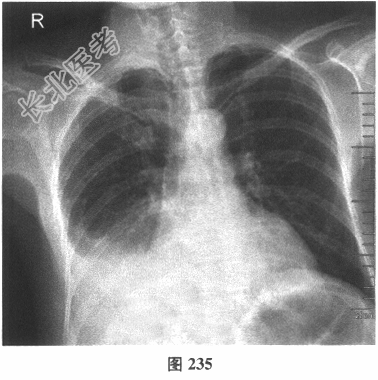

- 多项选择题3.[提示]患者入院后查体:右下肺呼吸音消失, 无干湿性啰音,叩诊呈实音。查胸部X线片(图235)提示右下肺大片高密度影, 呈内低外高弧形。为明确诊断,患者还应完善下列哪些检查( )